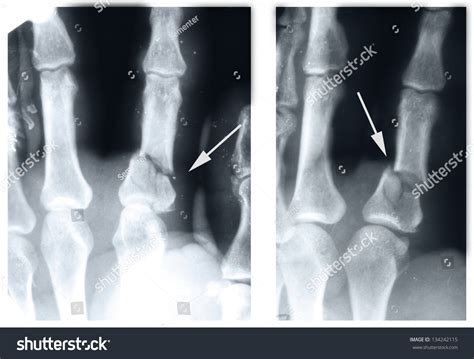

Diagnosing a Broken Index Finger

Diagnosing a broken index finger typically involves a physical examination and imaging tests. Your healthcare provider will:

• Examine the injured finger to assess the extent of the damage.

• Order X-rays to visualize the bone and determine the type and severity of the fracture.

• In some cases, additional imaging tests such as CT scans or MRIs may be required for a more detailed view.

Based on the findings, your healthcare provider will recommend the appropriate treatment plan.